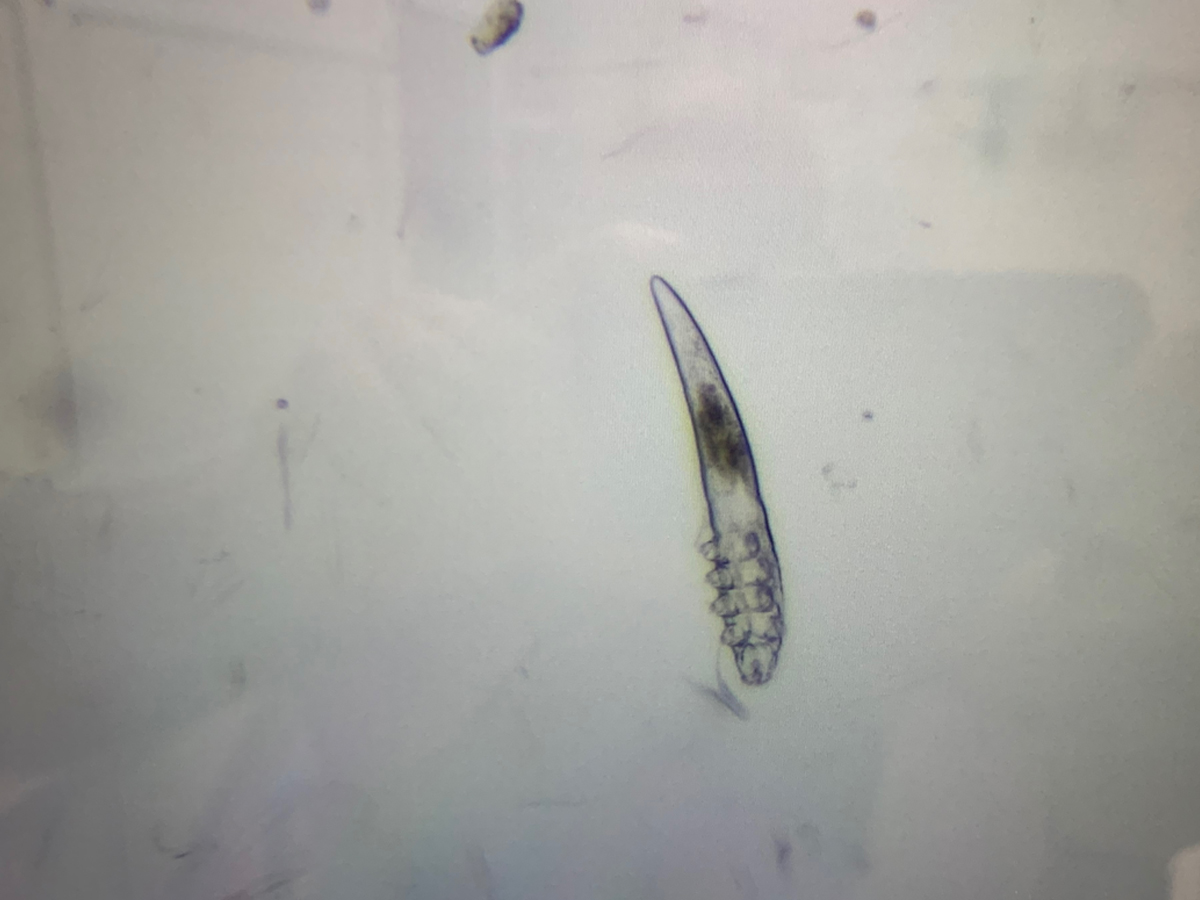

Животному были выполнены следующие диагностические манипуляции: глубокий соскоб кожи, трихоскопия, мазок отпечаток из под струпа. В соскобе и трихоскопии обнаруживалось большое количество клещей из рода Demodex. В мазке отпечатке было значительное количество бактериальной флоры.

Жужику был поставлен диагноз - ювенильный генерализованный демодекоз. Состояние осложняла вторичная пиодермия, что и давало такой сильный зуд.